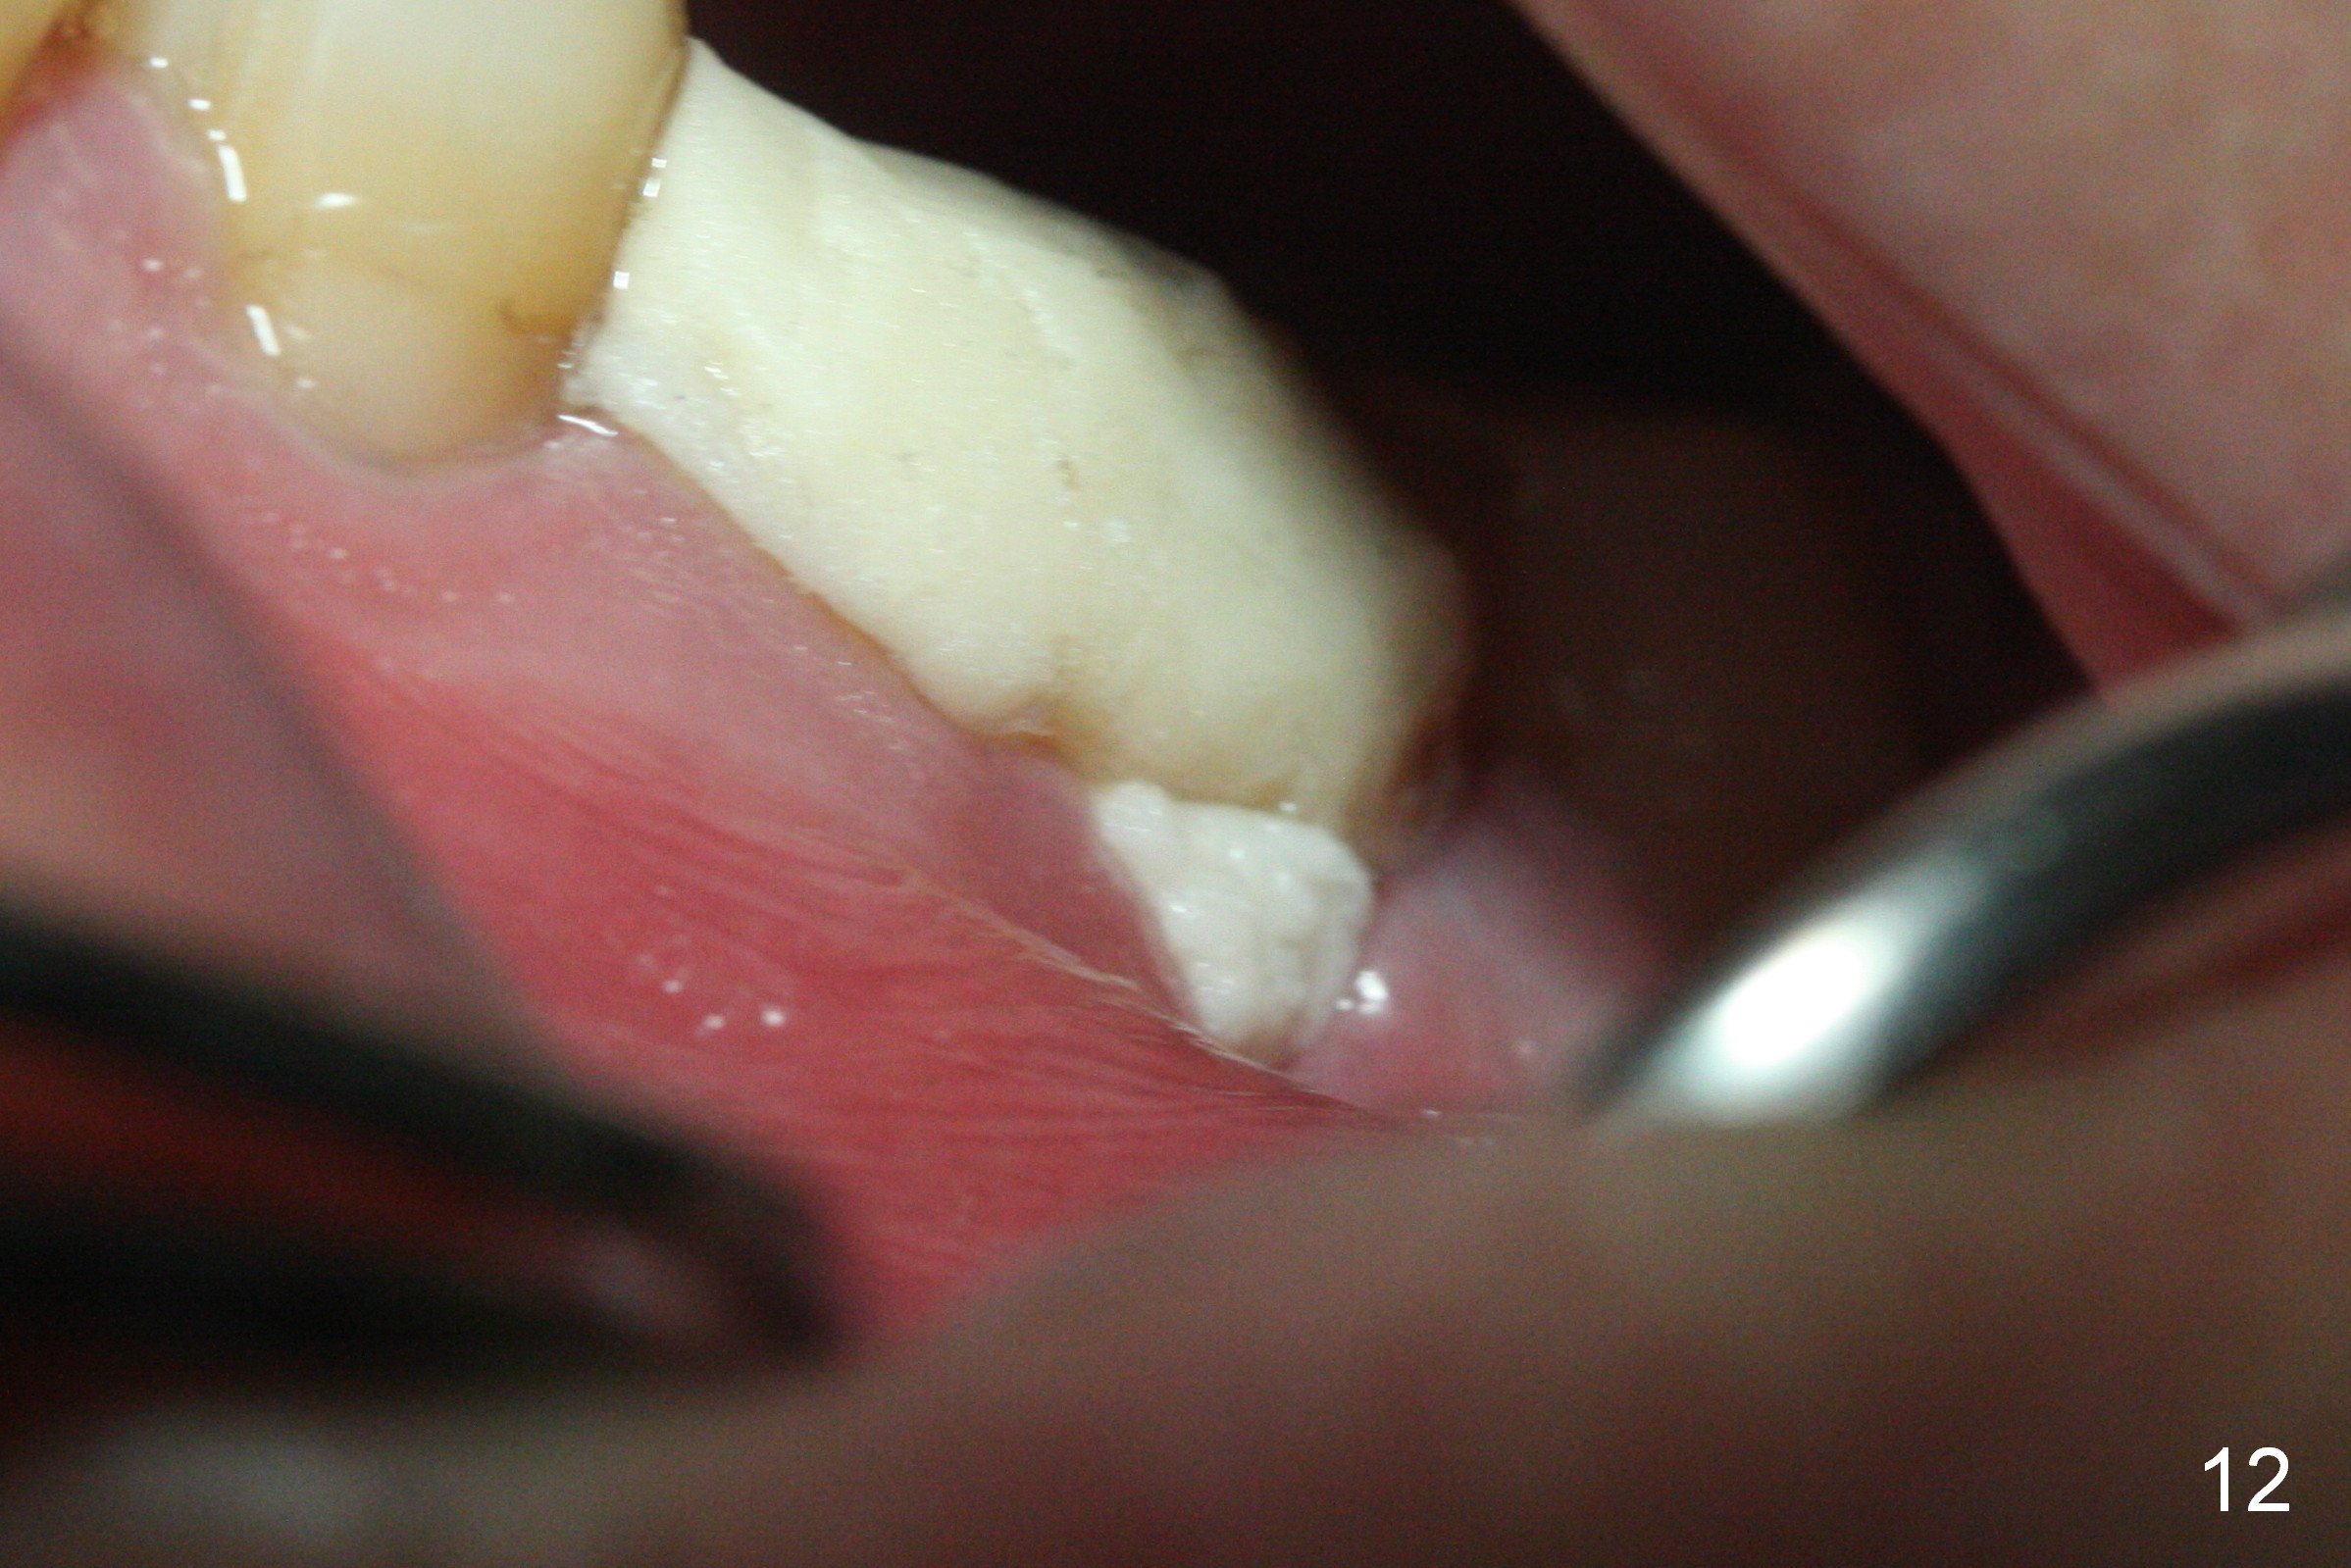

The mild postop pain lasts ~ 6 days with loss of bone graft for the 1st two days postop. Midbuccal dehiscence is found 7 days postop (Fig.11). After Chlorhexidine irrigation, a piece of Osteogen plug is inserted (Fig.12), followed by closure of the wound with a new layer of acrylic (Fig.13). It appears that placing a piece of collagen membrane against buccal plate before bone graft is not secure. Preferably, PRF membrane(s) should be used instead to facilitate wound healing internally, followed by externally acrylic coverage (to prevent bone graft from dislodgment if the membranes do not prevent dehiscence). Most importantly, do not hesitate to harvest blood for PRF if indicated. Once making it, keep it moist with the PRF box cover.